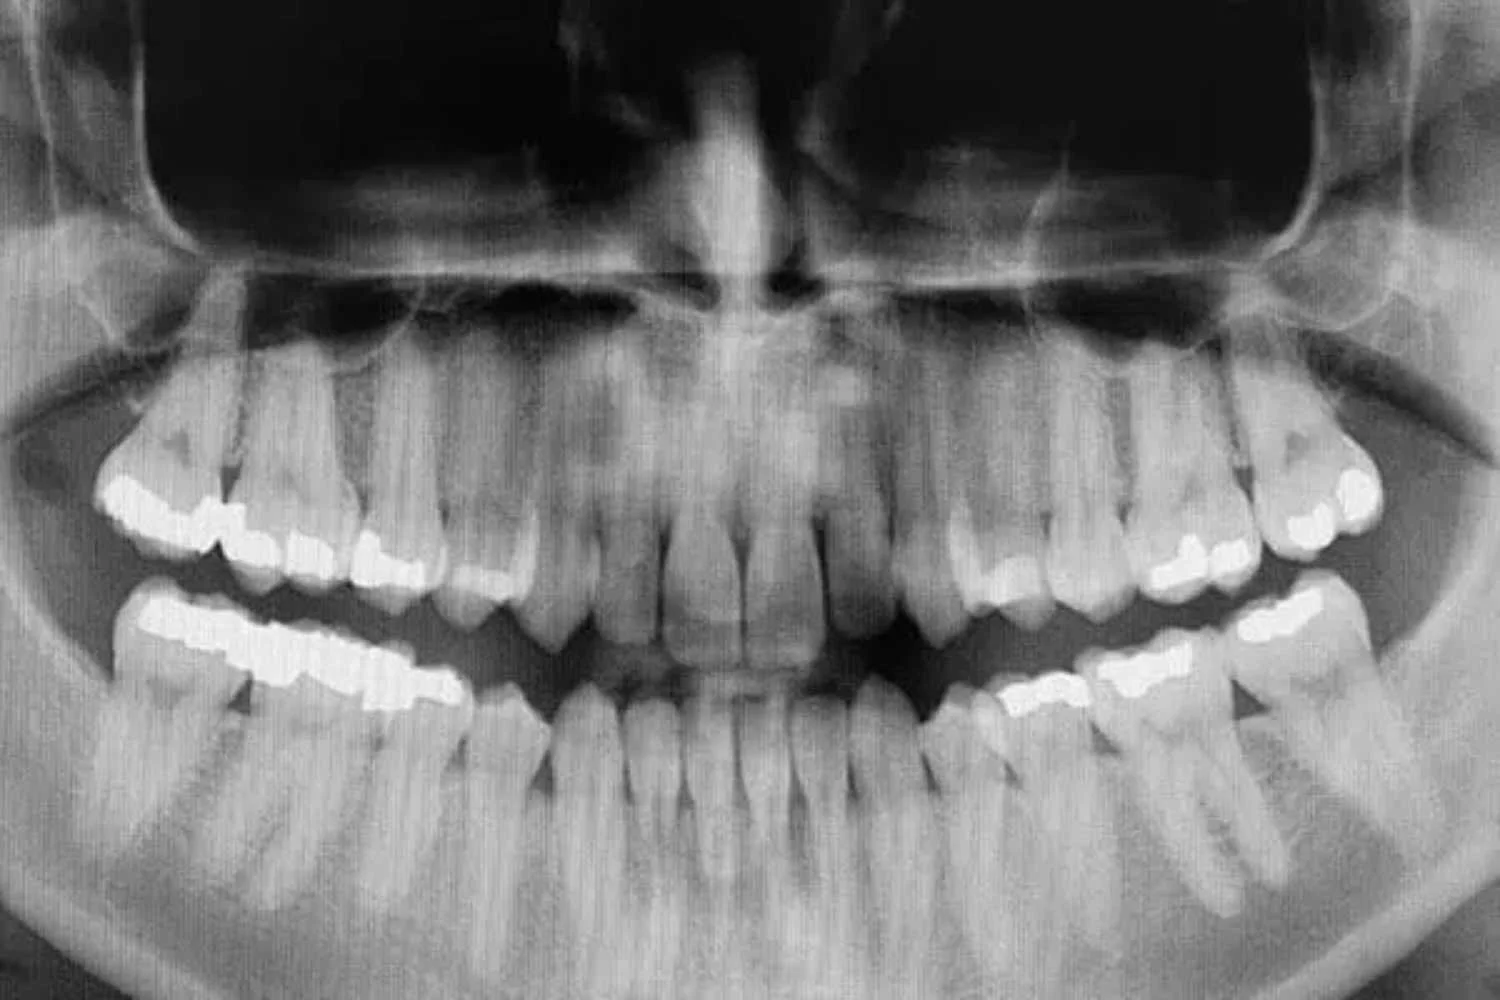

Sample Xray Image

Cone Beam technology provides a digital tomographic 3D view of the patient’s area of interest. A traditional x-ray is only two-dimensional. With Cone Beam systems the doctor is able to get a full 360-degree view of the tooth and all surrounding areas. The 3D Cone Beam scanner provides nearly limitless views of the teeth while using less radiation than traditional medical CT technology. This new technology is fast, simple, and painless, providing many wonderful benefits that were unavailable only a few years ago.